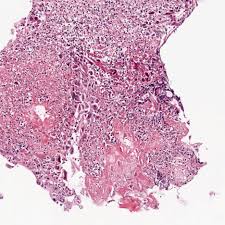

Hsv Esophagitis Pathology / Pathology Of The Esophagus - Peptic strictures cause a gradually progressive dysphagia for solid foods.. Common forms of esophagitis include reflux esophagitis, infectious esophagitis, pill esophagitis candida esophagitis (see the image below) is the most common type of infectious esophagitis. Cytomegalovirus esophagitis is a form of esophagitis associated with cytomegalovirus. The latter can occur frequently during anesthesia or deep sedation. Herpes esophagitis is a viral infection of the esophagus caused by herpes simplex virus (hsv). The esophagus is a tube composed of a mucosal lining, and longitudinal and circular smooth muscle fibers.

This condition occurs in the setting of patients with a weakened immune system who are susceptible. Cobblestone esophagitis (эзофагит со слизистой булыжной мостовой). The esophagus is a tube composed of a mucosal lining, and longitudinal and circular smooth muscle fibers. Herpes esophagitis is a viral infection of the esophagus caused by herpes simplex virus (hsv). Esophagitis can occur from irritation from toxic or abrasive materials ingested or from gastric reflux.

Pathology Of Herpes Simplex Virus Infection Dr Sampurna Roy Md from www.histopathology-india.net This condition occurs in the setting of patients with a weakened immune system who are susceptible. Esophagitis can occur from irritation from toxic or abrasive materials ingested or from gastric reflux. Infective esophagitis is a rare disease, affecting mostly immunocompromised patients. Very few cases of a multiple viral infection have been reported. Cobblestone esophagitis (эзофагит со слизистой булыжной мостовой). The latter can occur frequently during anesthesia or deep sedation. Healing and relapse of severe peptic esophagitis after treatment with omeprazole. Causes of esophagitis include stomach acids backing up into the esophagus, infection, oral medications and allergies.

Cytomegalovirus esophagitis is a form of esophagitis associated with cytomegalovirus. Herpes esophagitis is a viral infection of the esophagus caused by herpes simplex virus (hsv). Herpes esophagitis is a viral infection of the esophagus caused by herpes simplex virus (hsv). Symptoms include dysphagia, upper abdominal pain, diarrhea, nausea, vomiting, and sometimes hematemesis. Very few cases of a multiple viral infection have been reported. Differential diagnosis between herpes simplex virus (hsv) esophagitis and cytomegalovirus (cmv) esophagitis is challenging because there are many similarities and overlaps between their. Common forms of esophagitis include reflux esophagitis, infectious esophagitis, pill esophagitis candida esophagitis (see the image below) is the most common type of infectious esophagitis. Swallowed food and liquids normally pass through it. Eosinophilic esophagitis attributed to gastroesophageal re. Infective esophagitis is a rare disease, affecting mostly immunocompromised patients. Healing and relapse of severe peptic esophagitis after treatment with omeprazole. Esophagitis can occur from irritation from toxic or abrasive materials ingested or from gastric reflux. The esophagus is a tube composed of a mucosal lining, and longitudinal and circular smooth muscle fibers.

Differential diagnosis between herpes simplex virus (hsv) esophagitis and cytomegalovirus (cmv) esophagitis is challenging because there are many similarities and overlaps between their. Esophagitis can cause painful, difficult swallowing and chest pain. Healing and relapse of severe peptic esophagitis after treatment with omeprazole. Esophagitis can occur from irritation from toxic or abrasive materials ingested or from gastric reflux. Causes of esophagitis include stomach acids backing up into the esophagus, infection, oral medications and allergies. The latter can occur frequently during anesthesia or deep sedation. Very few cases of a multiple viral infection have been reported. Herpes esophagitis is a viral infection of the esophagus caused by herpes simplex virus (hsv). Esophagitis may cause odynophagia and even esophageal hemorrhage, which is usually occult but can be massive. We present a case of combined cytomegalovirus. Eosinophilic esophagitis attributed to gastroesophageal re. Swallowed food and liquids normally pass through it. Esophagitis, also spelled oesophagitis, is a disease characterized by inflammation of the esophagus.

Swallowed food and liquids normally pass through it. Esophagitis can cause painful, difficult swallowing and chest pain. Causes of esophagitis include stomach acids backing up into the esophagus, infection, oral medications and allergies. Common forms of esophagitis include reflux esophagitis, infectious esophagitis, pill esophagitis candida esophagitis (see the image below) is the most common type of infectious esophagitis. Symptoms include dysphagia, upper abdominal pain, diarrhea, nausea, vomiting, and sometimes hematemesis. Very few cases of a multiple viral infection have been reported. We present a case of combined cytomegalovirus. It connects the pharynx to the stomach; As the practice shows, hypodiagnostics of eosinophilic esophagitis and other eosinophilic gastrointestinal diseases takes place. Cytomegalovirus esophagitis is a form of esophagitis associated with cytomegalovirus. Esophagitis, also spelled oesophagitis, is a disease characterized by inflammation of the esophagus. Herpes esophagitis is a viral infection of the esophagus caused by herpes simplex virus (hsv). Infective esophagitis is a rare disease, affecting mostly immunocompromised patients.